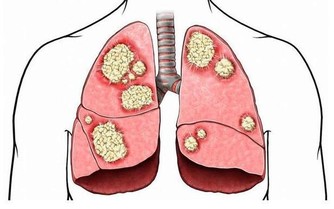

菠菜其實是在大家餐桌上經常會見到的一類蔬菜,它的營養價值十分豐富,能夠為人體提供身體所需的維生素以及多種微量元素,但大家也需要了解到的是,菠菜中往往還含有一種草酸成分,被人體攝入吸收後,會在體內形成草酸鈣結晶,這一物質會在一定程度上影響腎臟功能的正常排毒,並使得人體的解毒功能出現紊亂。